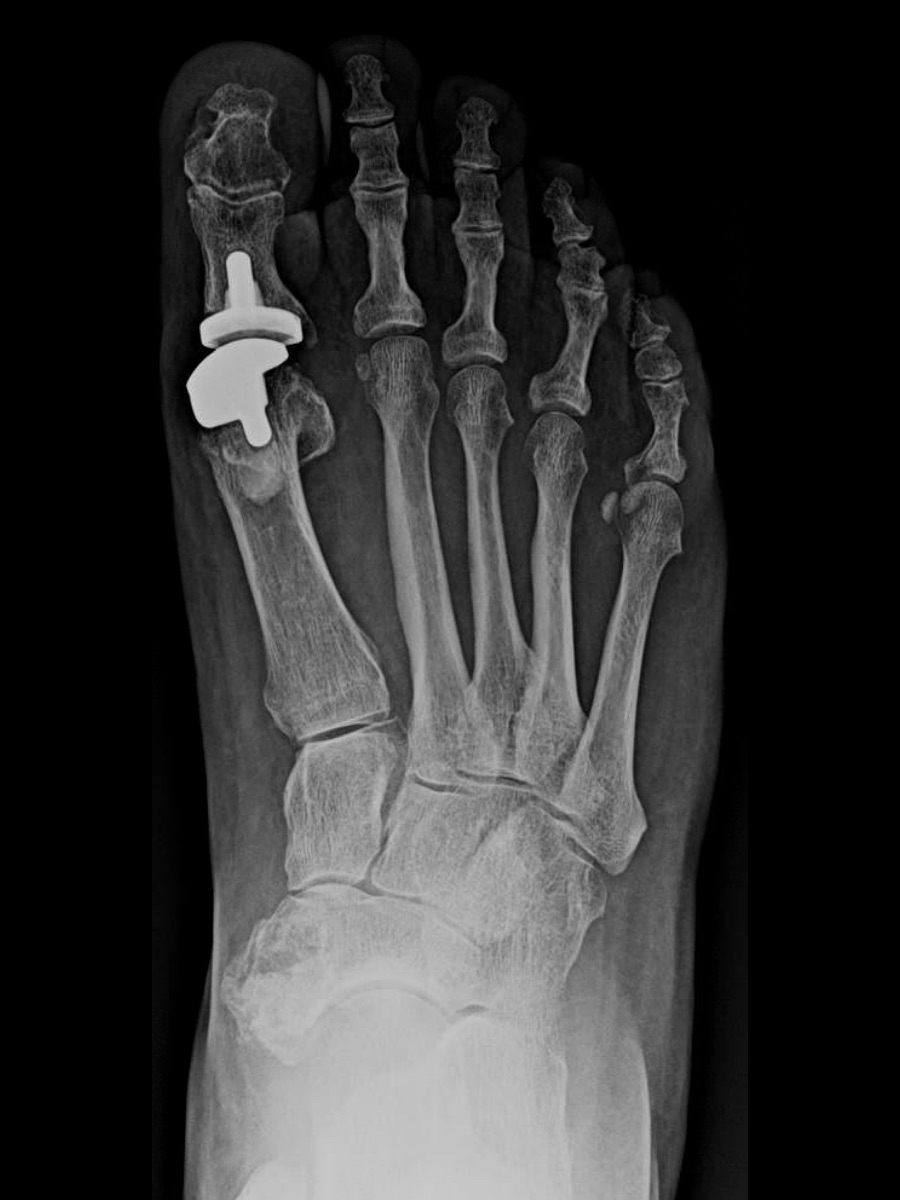

Practical Pearls On Revising A Failed Hallux HemiImplant Arthroplasty

From www.hmpgloballearningnetwork.com

Practical Pearls On Revising A Failed Hallux HemiImplant Arthroplasty Toe Joint Replacement Recovery Time Your recovery time depends on how extensive the procedure is and how well you take care of your foot after the procedure. Learn how a big toe replacement can relieve pain and stiffness caused by osteoarthritis or hallux rigidus. Find out what happens during surgery, how long it takes to recover, and what. Most patients go home the day after. Toe Joint Replacement Recovery Time.